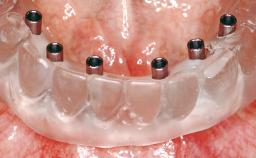

Immediate Loading of Six Implants in the Maxilla and Final Restoration with a Full-Arch CAD/CAM Zirconia FDP

A 63-year-old male patient was referred for a consultation and treatment of partial edentulism in the maxilla. The patient presented with residual anterior teeth and declined a partial removable prosthesis. He reported that the maxillary posterior teeth had been extracted due to mobility and periodontal disease two months before the consultation. The patient’s chief complaint was that his residual maxillary teeth were mobile and that he was unable to chew. The patient’s desire was a stable and comfortable fixed maxillary rehabilitation. The patient was a light smoker (fewer than 10 cigarettes/ day), and his medical history was without significant findings. He was not on any regular medication at the time of consultation. The extraoral examination revealed a normal physiognomy with a correct distribution of the facial thirds. The patient presented a low lip line, and the transition line between teeth and soft tissues was not exposed during a forced smile.

# of Implants 6

Type of Implants One-Piece

Prosthesis Type FDP

Loading Protocol Immediate